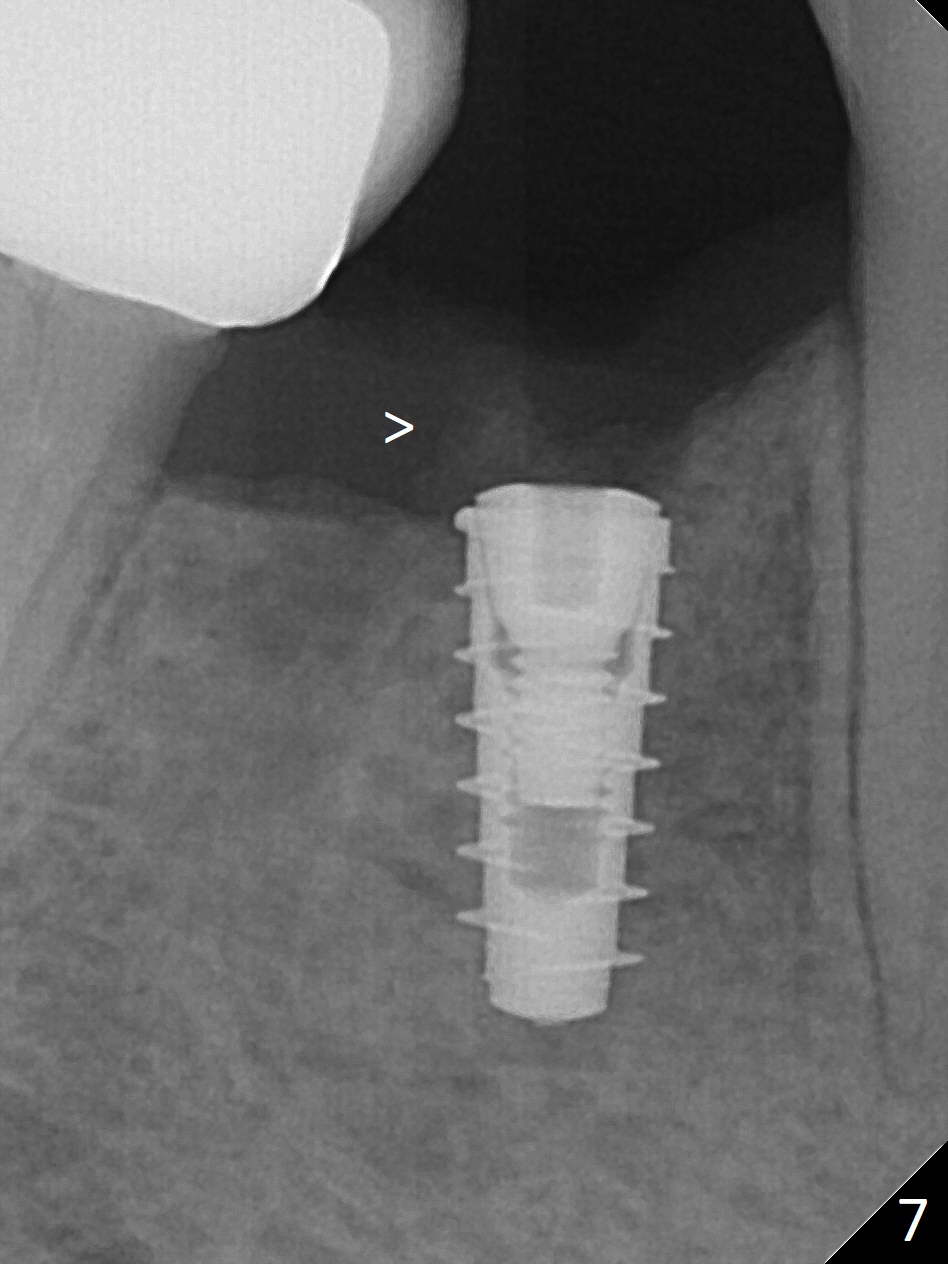

The patient returns for implant placement 11 months post extraction of #28 and 29. With flapless manner, initial osteotomy happens to drop into the original socket of #28 (Fig.4). After use of 3.3 mm Magic Drill (MD) and Final Drill for 15 mm, a 4x11 mm dummy implant is placed (Fig.5). It appears that the implant is long for the site (red dashed line: Mental Loop). However, a definitive implant (4x9 mm, IBS) has difficulty to reach its depth (Fig.6). After several rounds of untorque and retorque, the implant does not seat completely (Fig.7, implant driver disengagement) with autogenous bone placed distal (>). Retrospectively, a larger MD should have been used (3.8 mm) for complete seating in the dense bone. In fact she is post breast cancer treatment with 50% chance of relapse. The patient returns for follow up 1.5 months postop (Fig.8). The wound has healed. Impression is taken 5 months postop (Fig.9). When the crown is cemented, food impaction is an issue between the implant crown and crown at #30. Since the tooth #30 is mesially tilted with distal open margin and apical infection, the tooth will be extracted. Osteotomy is going to be initiated in the mesial slope of the mesial socket (Fig.9 red line). An implant will be placed more or less in the mesial socket (green box).